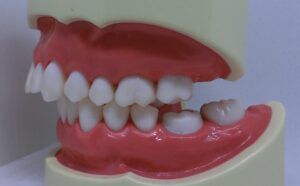

噛んでいるとはこういうことです。

噛んでいるということを理解できたでしょうか?

さて、近頃の可愛い女性の歯並びはどうなのでしょうか?

お見せします。

どうですか?びっくりでしょう?